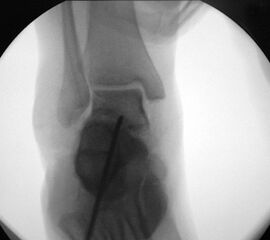

Abbildung 3

Schraubenfehllage: Bei der intra-operative Röntgen-Kontrolle muss der Fuß exakt seitlich und das obere Sprunggelenk ap eingestellt werden, um die korrekte Lage der Schrauben beurteilen zu können.